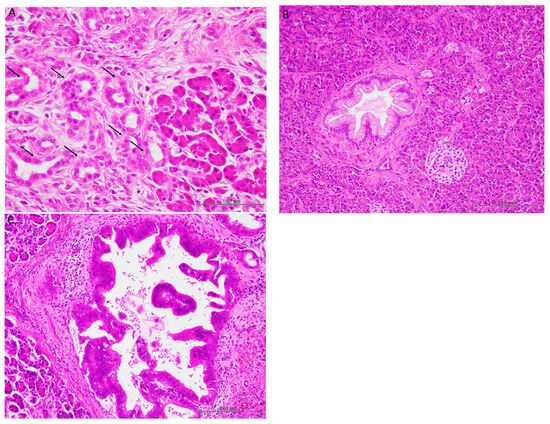

3.2. Histopathological Characteristics

3.3. Immunohistochemical Characteristics